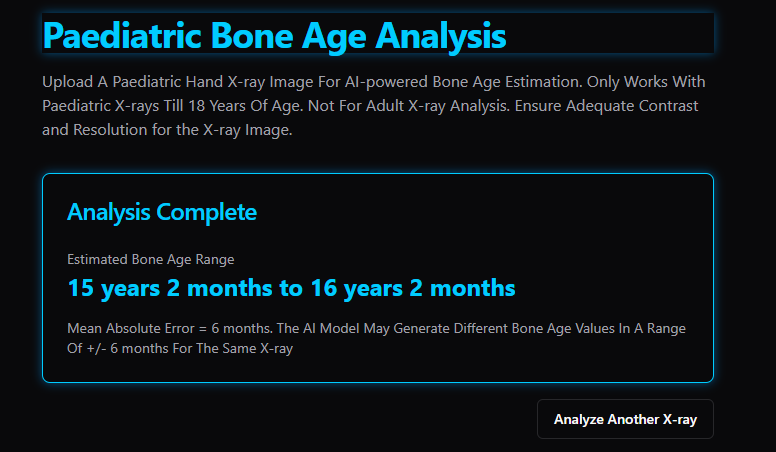

these AI's told me my bone age looks like 18 and 13. YES THIS BONE AGE AI WEBSITE SAID MY BIOLOGICAL AGE LOOKS 13 ACCORDING TO THE XRAY.

these AI's told me my bone age looks like 18 and 13. YES THIS BONE AGE AI WEBSITE SAID MY BIOLOGICAL AGE LOOKS 13 ACCORDING TO THE XRAY.